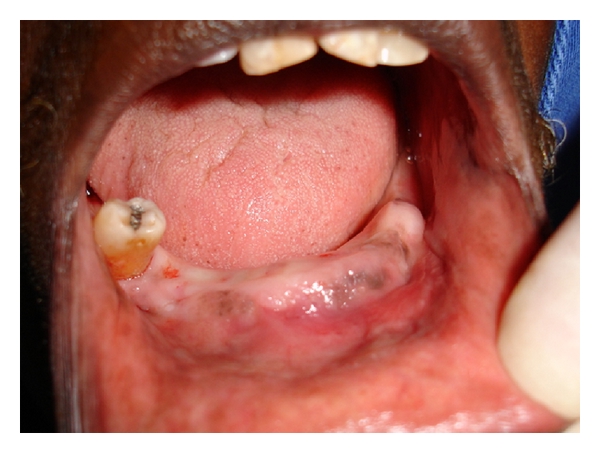

Case 1. A 77-year-old white female was seen at the Oral Medicine Clinic of the Federal University of Alfenas (UNIFAL-MG) with an asymptomatic, smooth surfaced, normal colored tumor on the anterior mandibular alveolar ridge, with two months evolution. A drainage point with purulent material was also present (Figure 1(a)). The patient’s medical history was unremarkable and no changes were noted on extraoral examination. Radiographic examination revealed osteolysis and bone sequestration on the mandibular alveolar ridge (Figure 1(b)). Based on clinical and radiographic findings, a provisional diagnosis of osteomyelitis was rendered. The patient was given amoxicillin (500 mg, three times/day) for 15 days and subsequently underwent excision of the bone sequestrum and curettage of the granulation tissue (Figure 2). The material was submitted to histopathological examination which revealed nonviable bone and a mixed inflammatory infiltrate of lymphocytes and plasma cells, confirming the diagnosis of chronic suppurative osteomyelitis. The area healed appropriately within one month (Figures 3(a) and 3(b)). The patient has been under follow-up for 5 years with no signs of recurrence.

(a)

(b)